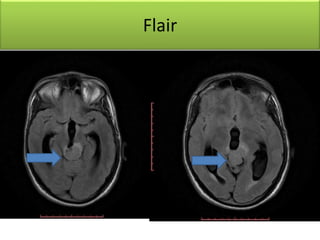

Flair

• Soft tissue mass lesion measureing2.9 X 2.7 X 2.7 cm

• Hypointense T1,hyperintense T2 / FLAIR signal &

homogenous post-contrast enhancement

• Lesion is compressing the superior portion of the cerebral

aqueduct with moderate supratentorial hydrocephalus